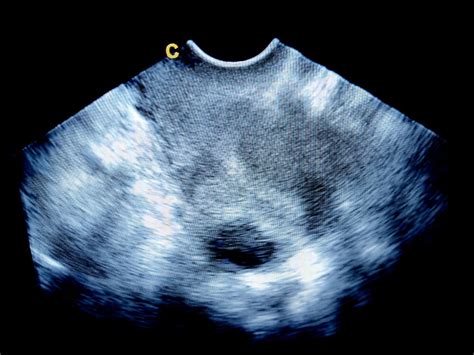

Miomi maternice (uterini leiomiomi) so benigne mišične in vezivne spremembe v miometriju; razlikujejo se po velikosti, obliki in hitrosti rasti. Prisoten je lahko en sam miom ali več hkrati, pri čemer jih »pogosto le s težavo ločimo od povečanega jajčnika«, odgovarja Jernej Bernik dr. med., spec. Miomi sodijo med najpogostejše benigne tumorske spremembe na steni maternice. Pojavnost: približno 20 % žensk, starejših od 30 let; 70-80 % žensk ima miome do 50. »Večje tveganje za pojav miomov imajo ženske med 40. in 50. letom … prav tako tiste z družinsko anamnezo, pri temnopoltih ženskah in pri ženskah, ki niso rodile.« - dr. »Miomi so benigne tvorbe mišičnega sloja maternice in sami po sebi niso nevarni, lahko pa težave povzroča njihova velikost, število ali položaj.« - dr. »Spremembe lahko do določene meje razlikujemo z ultrazvokom; dodatno pomoč predstavlja tudi magnetna resonanca«, pojasnjuje dr. Miomi ali maternični fibroidi so okroglaste tvorbe, ki ležijo tik pod površino maternice. Lahko so majhni kot grahovo zrno in povsem nemoteči ali pa veliki kot teniška žogica. Največkrat zraste en samostojen miom, v nekaterih primerih pa se pojavijo številni. Najpogosteje se začnejo pojavljati med 35. in 45. Vzroki za njihov nastanek niso še povsem pojasnjeni. Pomemben dejavnik za nastanek je hormonsko neravnovesje. V večini primerov je pojav miomov povezan z nenormalnim delovanjem jajčnikov, kar je posledica nihanja količine hormonov estrogena in progesterona. Raven fizične aktivnosti dodatno vpliva na nastanek miomov. Ženske, ki niso redno fizično aktivne, imajo višje tveganje za razvoj omenjenih tvorb. Na nastanek naj bi prav tako vplivala starost, pri kateri ženske dobijo prvo menstruacijo. Zgodnejša menstruacija nekoliko poveča tveganje za nastanek miomov, saj se stena maternice začne prej spreminjati, s čimer se poveča možnost za napake. Raziskave so pokazale celo razlike med ženskami različnih etičnih pripadnosti.